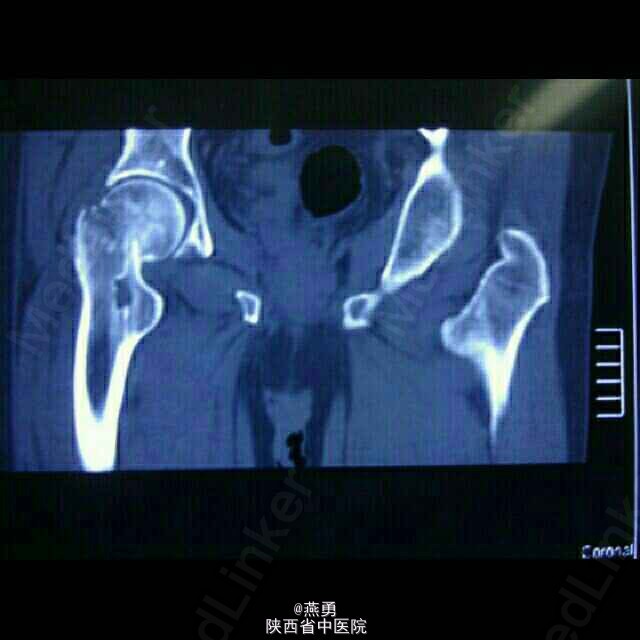

81岁男性患者,一个月前不慎摔倒右髋部着地,当即右髋部疼痛,活动困难,被动活动疼痛明显加重,近来患者自觉疼痛无缓解,活动受限,遂到我院就诊。 患者五年前曾在其他医院行结肠癌根治术 。

右下肢外展外旋畸形,较健侧短缩1CM,右髋关节肿胀不明显,压痛(+), 右腹股沟中点压痛(+),右下肢纵轴叩击痛(+)。

诊断:右股骨颈骨折,骨囊肿待查。治疗:右侧人工股骨头置换术,病灶清除探查术。麻醉生效后,常规逐层切开及暴露可见股骨颈颈中型骨折,清除周围纤维增生挛缩及瘢痕组织,取头器取出断裂的股骨头,患肢内收外旋脱位后,截骨,髓腔开口及扩髓,探针可见小转子内测约0.5*0.8cm病灶空腔,内壁完整,刮除腔内病灶送病检,填入少量抗生素型骨水泥,装入生物型股骨柄,置入双动头股骨头假体,复位,见右侧髋关节屈伸旋转活动良好,未出现脱位,双下肢等长。冲洗,清点纱布器械后,放置引流,关闭伤口加压包扎。 术后安返病房行预防感染预防血栓及对症治疗。